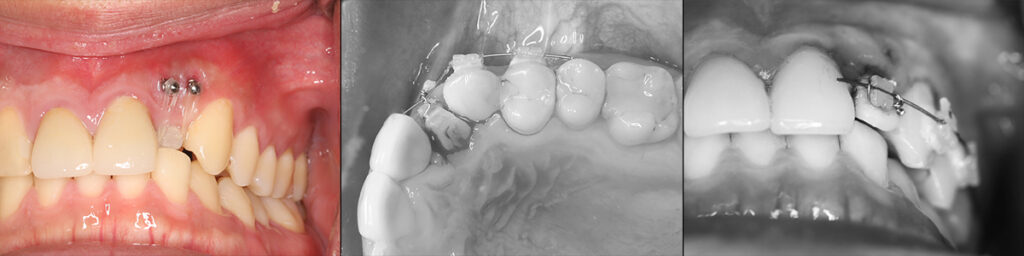

アンカースクリューによる圧下矯正と歯冠を歯肉下までスライスして前方傾斜移動

支台歯(修復前の形成歯)が対合前歯の前方に位置したら仮歯を装着し矯正は完了